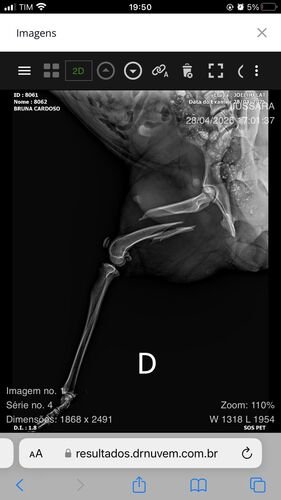

Oi, eu sou a Bruna!No sábado à noite, dia 26/04, fui surpreendida por um cachorro chamando a minha atenção para um mato, onde tinha muito lixo e uma outra cachorrinha deitada, sem conseguir levantar devido ao atropelamento que ocorreu no dia anterior, então ela estava a pelo menos 24h naquele local, com fome e dor. Resgatei os dois e apelidei de Cleitin e Jussara. Consegui ajuda para a consulta e exame de sangue, e também para a castração. O raio X da fratura foi particular e o laudo mostrou a necessidade de uma cirurgia ortopédica. O valor social que encontrei foi R$2600,00 e ainda terá um custo mínimo de R$300,00 com os remédios, além dos medicamentos que já estamos dando (antiinflamatório e analgésico). Por isso eu e a Jussara precisamos da ajuda de todos. Ela sente muita dor devido a lesão e não pode ficar muito tempo sem a cirurgia.Você pode nos ajudar?